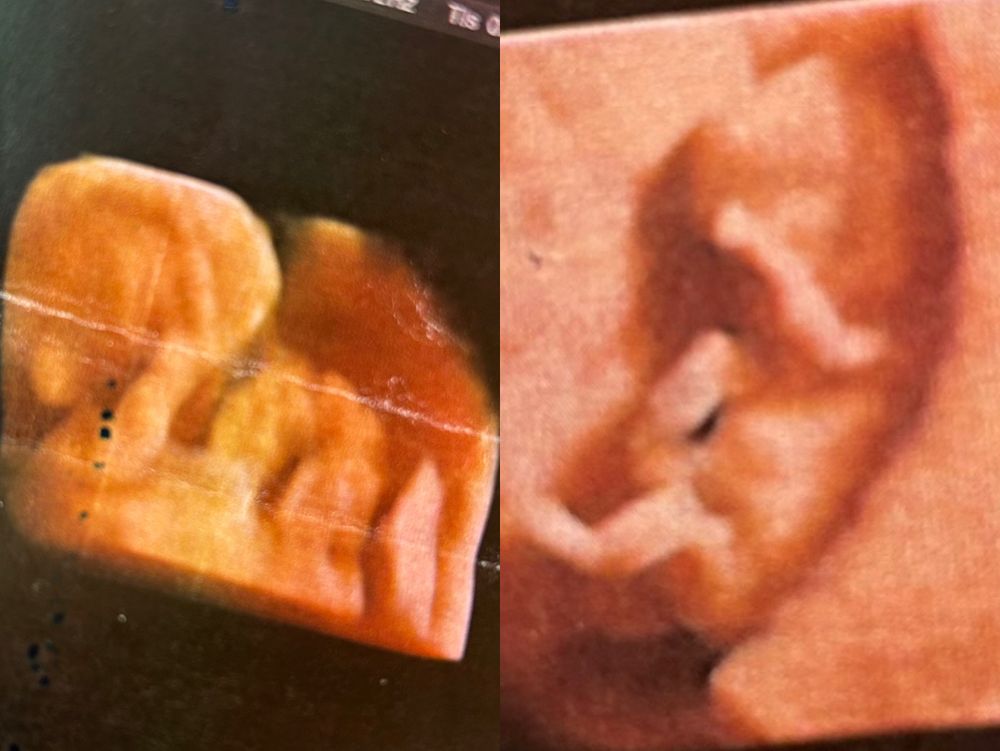

будут у меня Диана и Ви